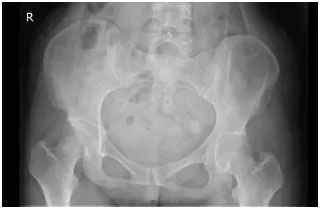

女性怀孕达到六周,身体开始分泌松弛激素。松弛激素能把骨盆周围韧带中40%-50%的Ⅱ型胶原蛋白拆解掉,使骨盆及周围的关节松弛,利于胎儿更容易地通过骨性产道。很多宝妈在分娩前就会出现骨盆失稳,导致耻骨联合分离和错位,骶髂关节或腰骶关节脱位和半脱位。

没有症状,没有影像证据,在传统医生的眼里就没有医疗必要性!然而更多的情况是:宝妈生完孩子面对裂开的骨缝,等待自然闭合,不去做专业骨盆闭合或矫正,继而形成“大屁股”、宽胯,骨盆出现松弛、分离,形状发生变化,导致产后单侧胯骨疼、腰疼、漏尿、同房不适,以及形体改变:腰椎侧弯、高低胯、宽胯等产后问题。

骨盆歪斜

骨盆,是整个身体的中心,是人体骨骼的中心,上到脊柱、下到两腿关节,都需要骨盆居中策应、调停,支持脊柱正直,统领两腿运动,女性在生产完,不管是顺产还是剖腹产,都会遇到一些症状:骨盆变大、胯骨变宽、骨盆前倾、腰痛、耻骨联合痛、O型腿、长短腿等力学上的不平衡的问题。产后医疗级美式汤姆森骨盆闭合使肌肉和骨骼的功能至恢复至良好状态。